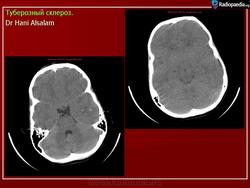

Туберозный склероз

Приложения:

1.tub_.slayd26.jpg2.tub_.slayd27.jpg3.tub_.slayd28.jpg4.tub_.slayd29.jpg